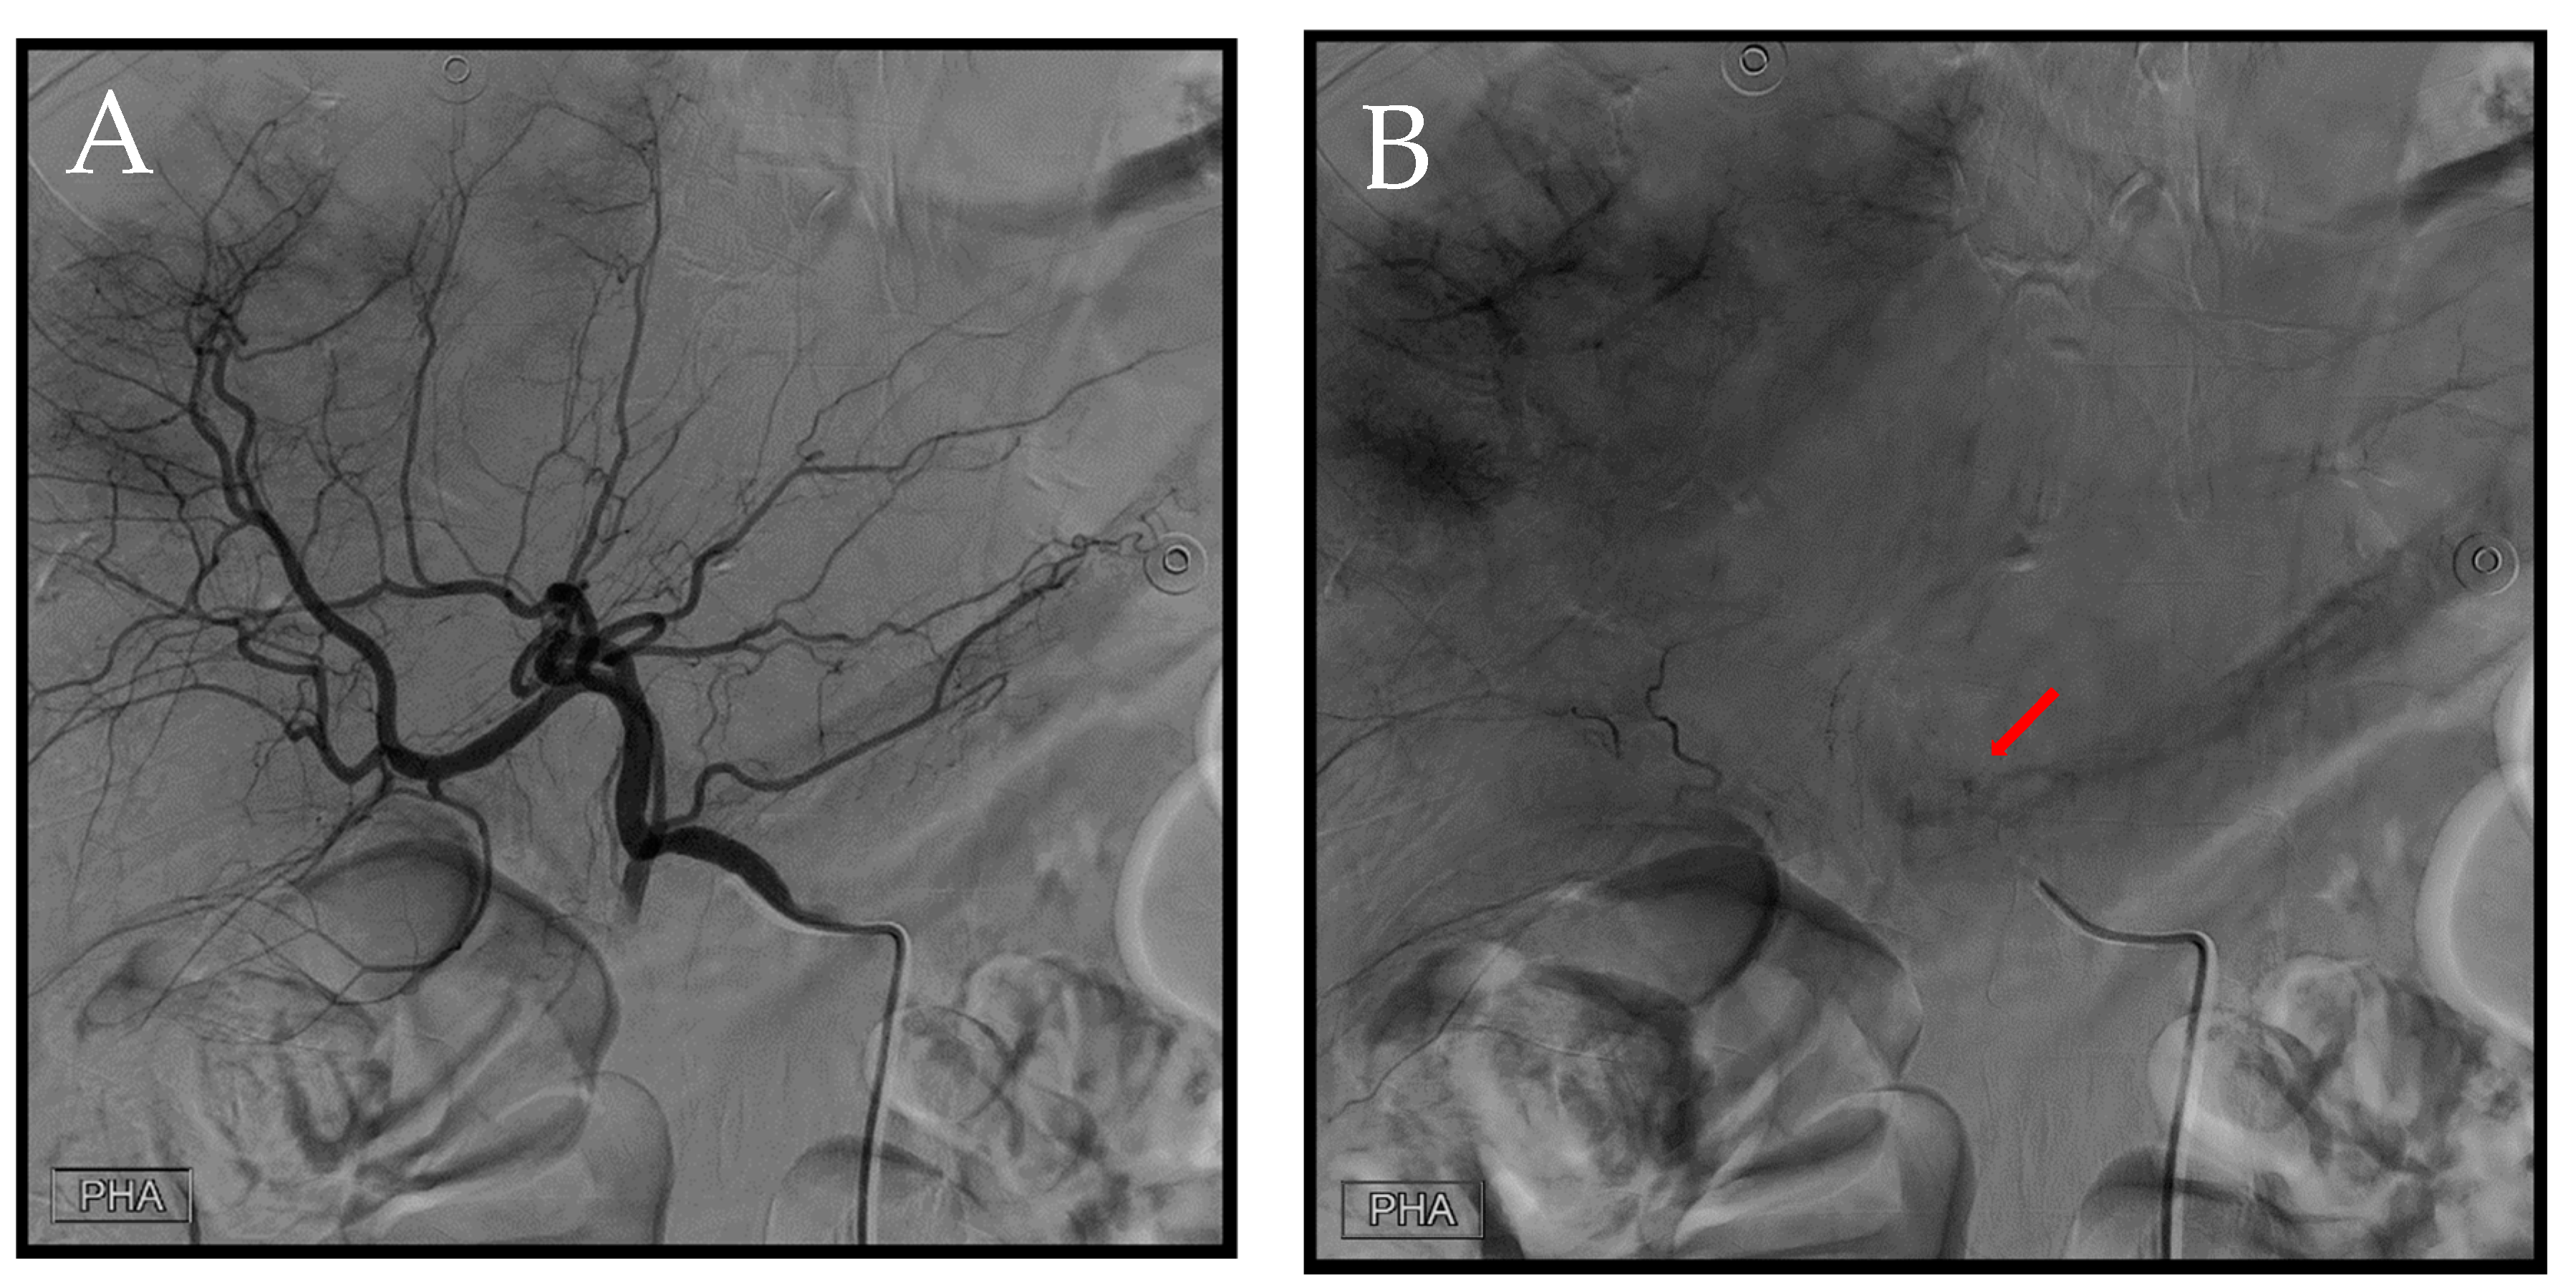

Figure 6. Representing the second transcatheter arterial embolization (TAE) session. (A) Angiography was performed using a 4Fr. RH catheter in the proper hepatic artery. (B) A distinct extravasation (arrow) was identified during this angiographic series.